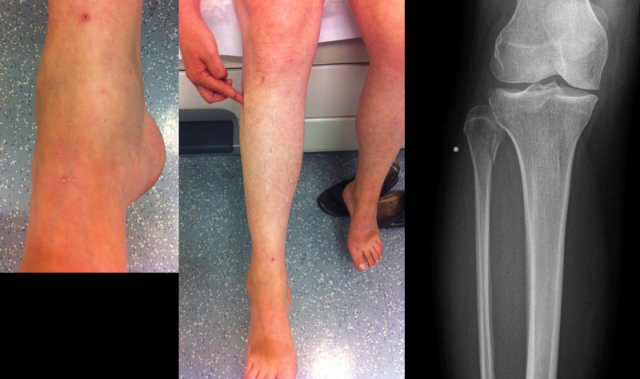

Example 3

In this case no fracture is seen, but only soft tissue swelling on the medial side.

In such a case, you have to rule out a Maisonneuve fracture, which is a high Weber C fracture.

Additional x-rays of the lower leg were taken.

There is a high fibula fracture.